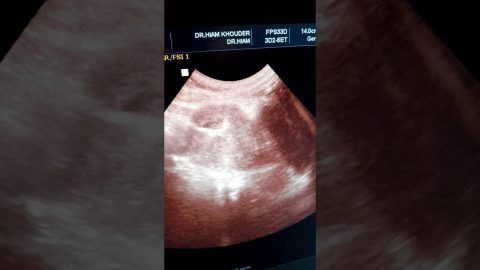

يعد اللولب الهرموني أو “لفيفة ميرينا” أحد وسائل منع الحمل ويأتي على شكل حرف T مصنوع من البلاستيك الطبي، تقتضي وظيفته على زيادة إنتاج هرمون البروجسترون الذي يساهم في تكوين بيئة معينة في الرحم تمنع وصول الحيوانات المنوية إلى عنق الرحم، وانعدام فرص قبول البويضة المخصبة في بطانة الرحم. وتدوم مدة اللولب الهرموني لمدة خمس سنوات وهي فترة طويلة نسبيا مقارنة بباقي وسائل منع الحمل.